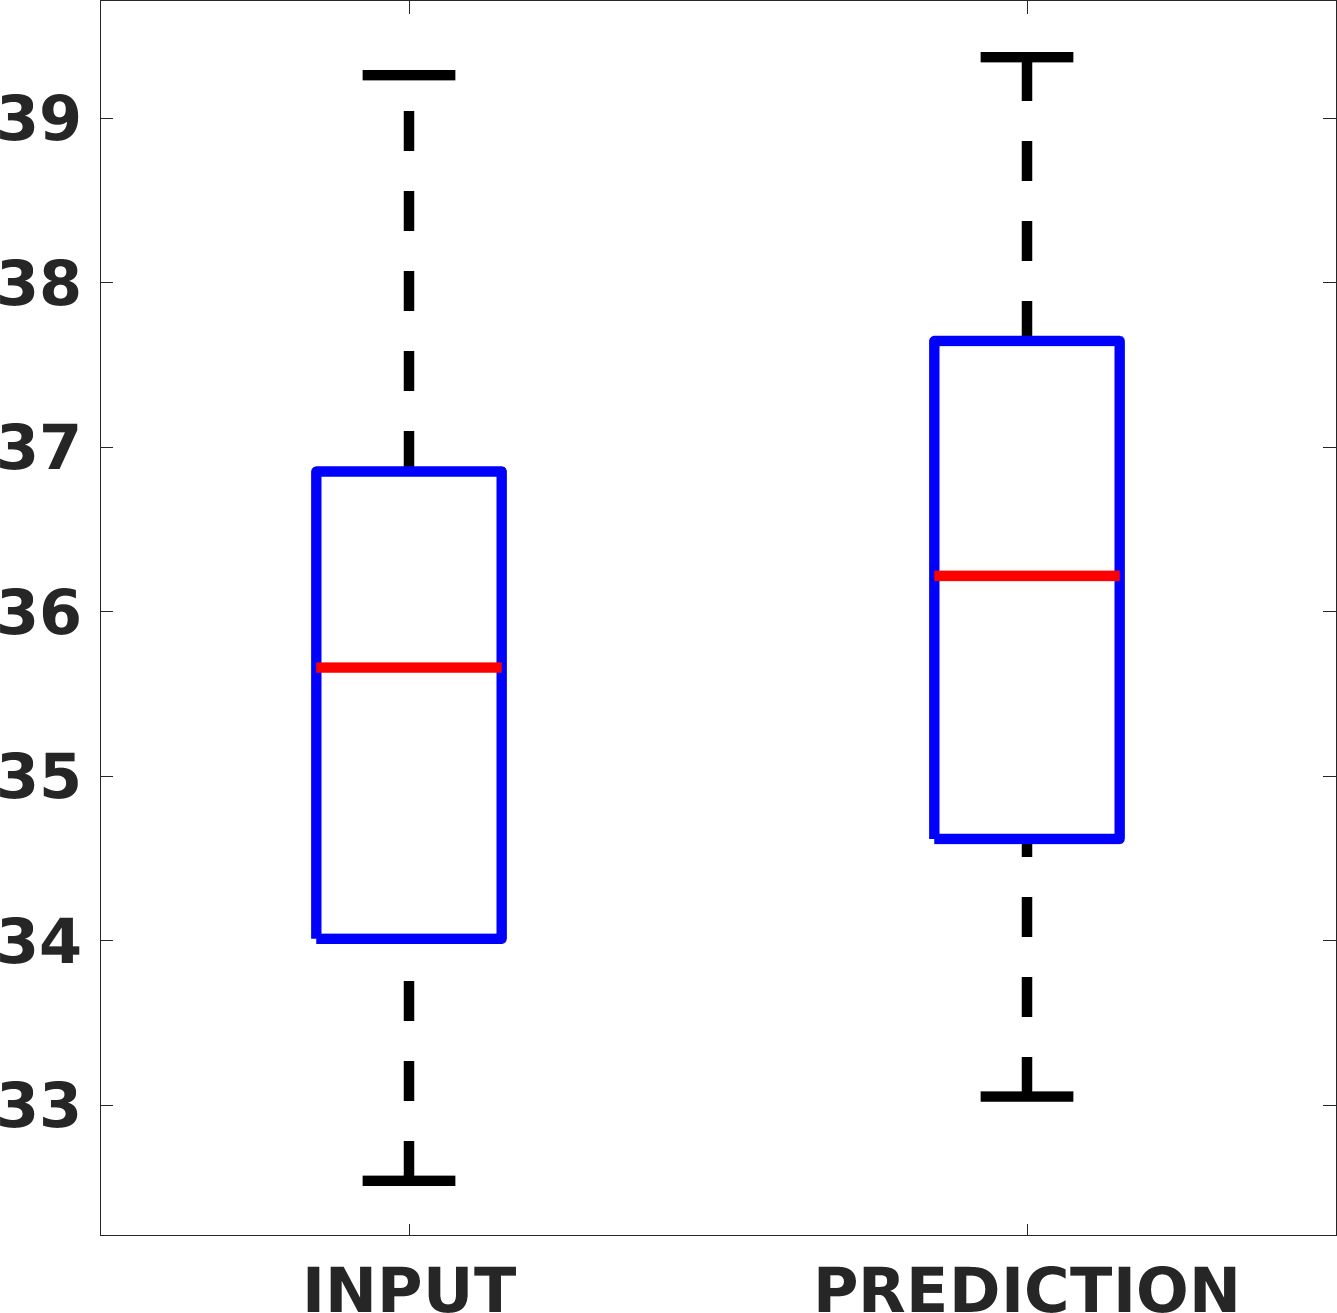

Fig. 7(a-b-c, left) shows the box plot of the statistics of the PSNR on three different anatomical districts, comparing the target images with the prediction and the cubic convolution, respectively. The metrics are computed on a data set of 200 images of the same district and with the same up-sampling factor. We report that the PSNR median value improves of on obstetric 2X raw images, on cardiac 2X raw images, and on abdominal raw 4X images.

Fig. 7(a-b-c, right) shows the histogram of the absolute value of the error with respect to the target image, of the prediction and Cubic convolution results, respectively. The histograms show the number of pixels where the prediction error is lower than 5 (i.e., the first bin of the histogram), which means very similar to the target when visually analysing the images. From the Cubic convolution to the predicted images, this value increases of on obstetric 4X raw images, on cardiac 4X raw images, and on abdominal 4X raw images.

Fig. 8 shows the box plot of the SSIM (a-b-c, left) and MAE (a-b-c, right) quantitative metrics, as performed for PSNR metric. Also, these metrics show that our method improves the results of Cubic convolution both in terms of average value and variability. For example, the SSIM median value improves of on obstetric 4X images and the MAE median value improves of on cardiac 2X images.

Fig. 17 (left) shows the box plot of the quantitative metrics, comparing the target images with the prediction and the Cubic convolution, respectively. The PSNR metric is computed on a data set of 200 images, belonging to the same district, and with the same up-sampling factor. Analysing the obstetric anatomical district and concerning the corresponding raw images (Fig. 7 (a, left)), the denoising allows the network to significantly improve the results of the up-sampling and the prediction. In particular, comparing the target images with the predicted images, the median PSNR value of obstetric 2X denoised images is 51.8, compared to the median PSNR value of obstetric 2X raw images which is 36.9.

Fig. 17 (right) shows the histogram of the absolute value of the error with respect to the target, of the prediction and Cubic convolution respectively. This result shows that our framework increase of and (2X and 4X, respectively) the number of pixels where the prediction error is lower than 5, which is very similar to the target when visually analysing the images, and improved with respect to the learning framework applied to raw images. According to Fig. 18, our method improves the accuracy of Cubic convolution. For example, the SSIM increases of on cardiac 2X and the MAE increases of on abdominal 4X.